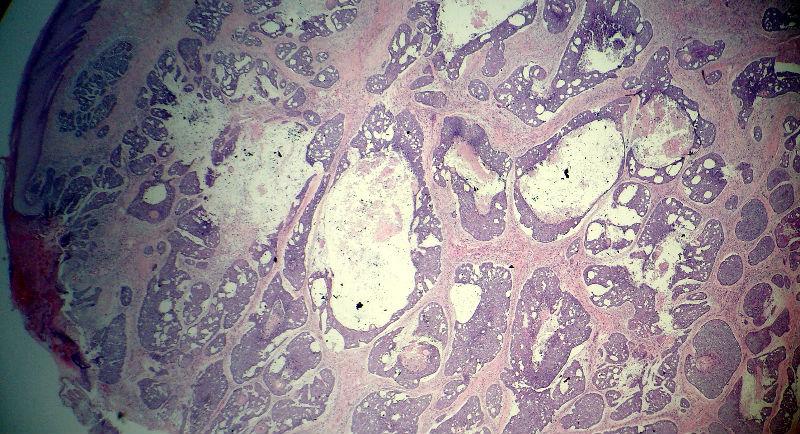

男,49岁,后枕部肿物3年,偶有破溃出血。

大体:皮肤半球形隆起,大小约2.3×2厘米,高出皮表0.8厘米,切面灰白,质地细腻。

基底细胞癌。

似乎既有腺样结构,也有角化珠形成,还有细胞团内的粉刺样坏死。

有坏死、囊肿、钙化及胆固醇样裂隙等结构

考虑外毛根鞘肿瘤,局部癌变。

大部分区域看着象基底细胞癌,后面几张(11-14)看着象是鳞癌。综合考虑基底细胞样鳞癌。